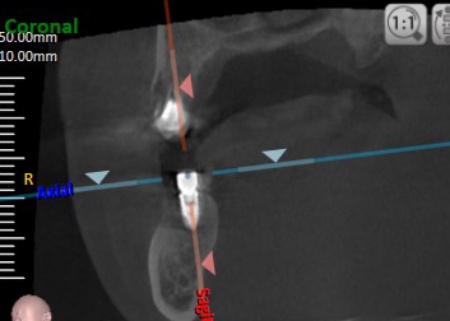

2ヶ月後に傷口がしっかりとふさがったことを確認できたため、CTを撮影してインプラントの治療計画を立て、後日インプラントを埋め込む手術を行いました。

手術の際、インプラントを埋め込む骨の中に抜歯後の傷が修復される過程でできた肉芽組織が見られたため、手術時に専用の器具を用いて取り除いてからインプラントを埋め込み、縫合しました。